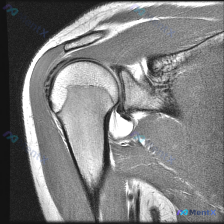

单张肩部MRI-T1冠状位,未发现盂唇撕裂直接证据,下一步该怎么查?

最近看到一份肩部MRI影像分析报告,患者怀疑盂唇病变(labral pathology),但在提供的T1冠状位序列上未发现盂唇撕裂的直接征象。 影像分析要点: - 骨性结构(肱骨头、肩峰、锁骨):未见明显骨质破坏/骨折,骨髓信号正常 - 关节对合:盂肱关节对合良好,无脱位 - 冈上肌腱:走行连续,信...

看到一个肩部MRI病例(T1序列、冠状位),原问题是关于盂唇病变的,但我在看的时候发现冈上肌腱的信号异常好像更明显。大家先看影像,你会怎么考虑?